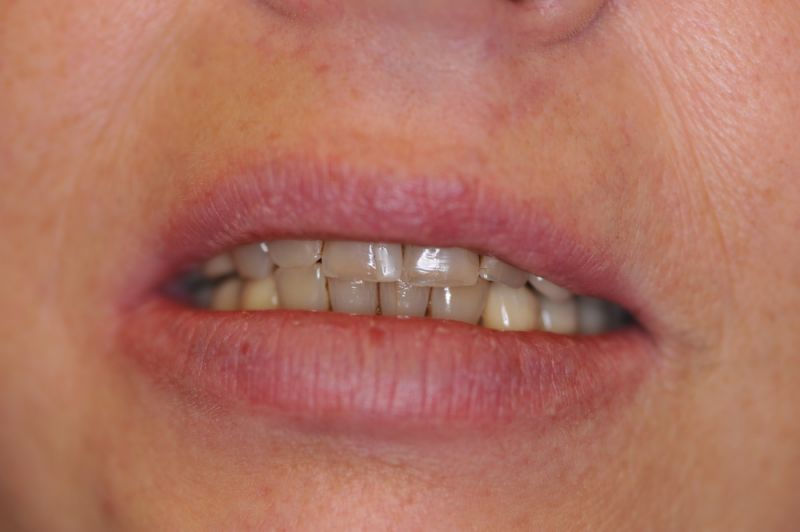

Schwierigster Fall aller Zeiten, praktisch beschwerdefrei. Patientin glücklich!

Der Fall einer Patientin aus Hamburg ist zwar bei weitem nicht der umfangreichste, oder gar teuerste Fall aller Zeiten, aber der Fall, der bei dem überschaubaren Umfang, das meiste Kopfzerbrechen bereitet hat und man darf es sagen, am Ende primär als sportliche Herausforderung gesehen wurde, ob man das überhaupt noch hinbekommt.

Es war eine Kombination aus Schmerzen bis an die Suizidgrenze, beschränkten wirtschaftlichen Möglichkeiten, sehr stark eingeschränkten Möglichkeiten der für Implantate zur Verfügung stehenden Knochenverhältnisse in einem stark atrophierten Unterkieferseitenzahnbereich und zudem dann auch noch durch auftretenden Problemen bei der Implantatinsertion und nachfolgenden Versorgung der Implantate.